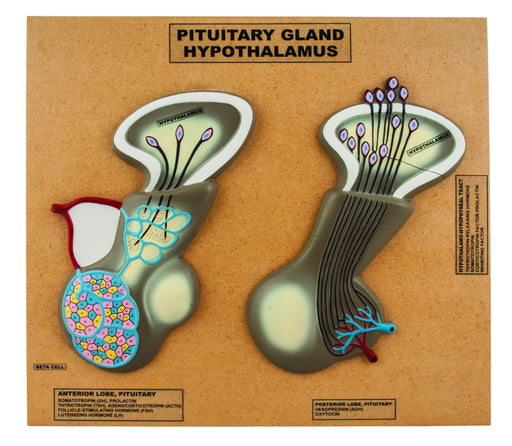

Eisco Labs Model of Pituitary Gland and Hypothalamus; Greatly Enlarged:

Greatly Enlarged Vividly hand painted Length: approx. 12" and Width: approx. 7" (at widest section) Base Dimensions: 18" X 16" Clearly Labeled The...

View full detailsAM0254 -